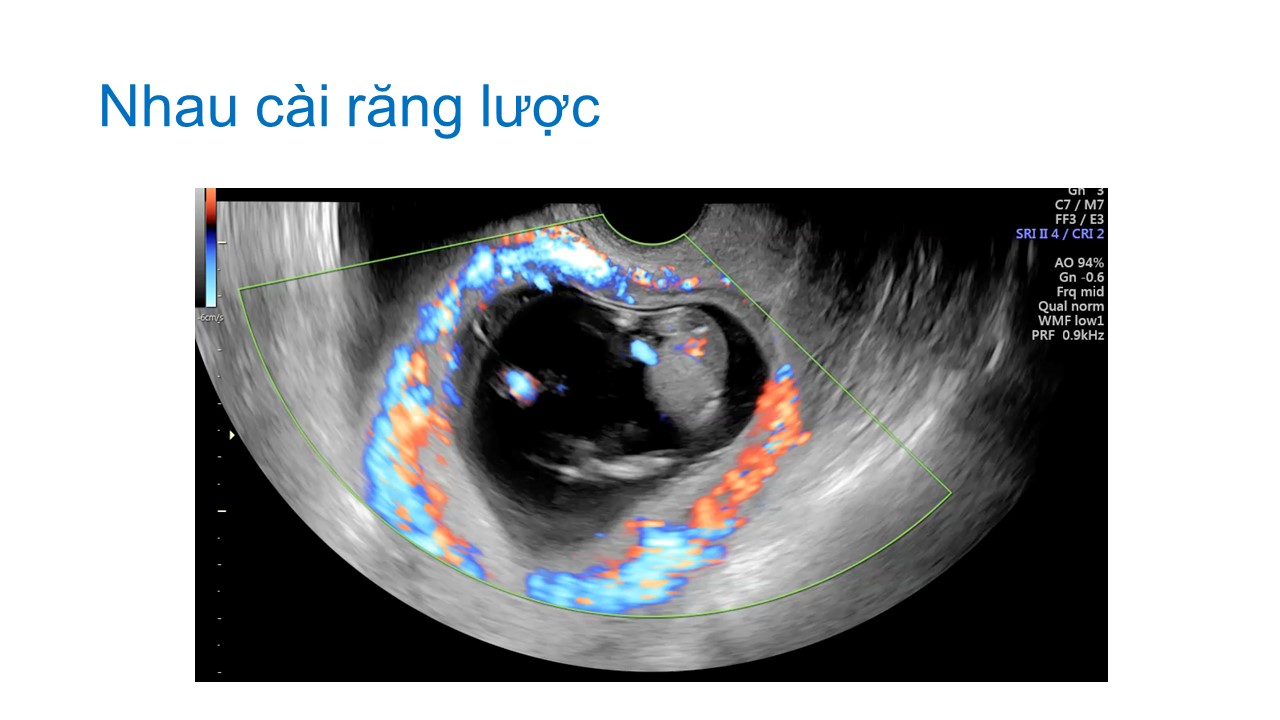

Siêu âm hình thai học quý I

ThS. BS CKII Nguyễn Đình Vũ - Khoa CĐHA, Bệnh viện Hùng Vương